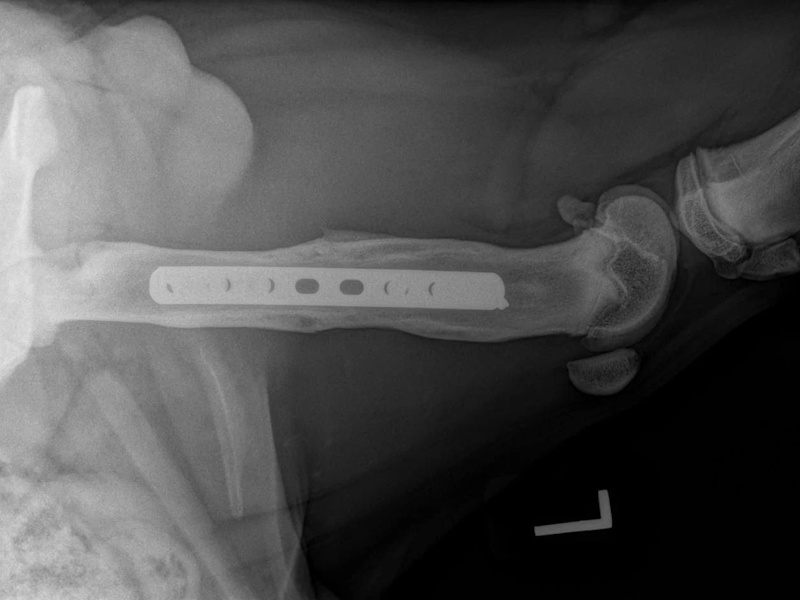

An osteotomy is a surgical cut in a bone. In the cruciate deficient stifle, a cut is made in the top of the tibia. The top portion of bone that contains the articular surface is rotated to level it. The two pieces of bone are held in place with a metal plate and screws.

Post Surgical Radiographs

While the patient is still anesthetized, the patient is taken into radiology for post-surgery radiographs (X-rays). The radiographs are assessed to measure the new tibial plateau angle. We are aiming for 5-6 degrees relative to the long axis of the tibia. The apparatus (plate and screws) are assessed for size and appropriate position.

Fore Limb (Humerus, Radius/Ulnar, Metacarpus)